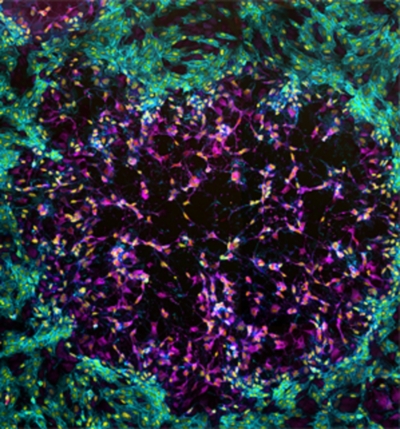

The striking image above, captured by University of Sydney researchers, shows the vaccinia virus — the vaccine used to beat smallpox — spreading from one cell to a whole layer of cells in a monkey’s kidney.

The goal of the experiment wasn’t to simply churned out a cool picture, but helps Dr. Timothy Newson and PhD student Dean Procter — both of the Australian National University’s School of Molecular Bioscience — understand how a virus causes disease after its genes have been mutated.

Like with mind-blowing images from space, this image is also a composite of various smaller images. The team only infected a few cells in order to monitor the natural spread of the virus, and after three days, the cells are fixed, which creates something of a still. After that, the researchers use colored chemicals to help differentiate parts of the still. In this image’s case, the pink-purple color shows infected cells, while yellow shows DNA and the turquoise shows the skeleton of the still.